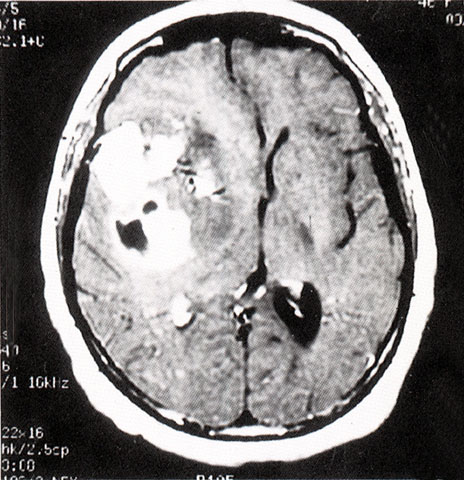

FH1053 脑胶质瘤(MRI)

光盘检索编码 FH1053  函授作业图编号 1053

图  名 脑胶质瘤(MRI)